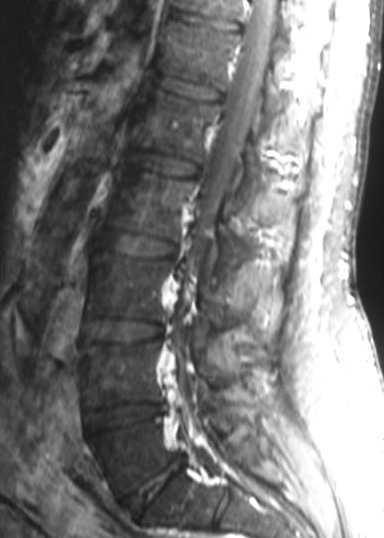

Se realizó una resonancia magnética (RM) de la columna lumbar (sin y tras contraste intravenoso) y se observaron, además de la masa retroperitoneal que comprimía la VCI, unas imágenes puntiformes y lineales hipointensas en todas las secuencias que ocupaban el espacio epidural adyacente al muro posterior de las vértebras lumbosacras, que se extendían a través de los agujeros de conjunción hacia las partes blandas perivertebrales (figs. 1-3). Esta alteración correspondía a estructuras vasculares dilatadas dependientes del plexo venoso epidural vertebral.

Fig. 2. Resonancia magnética ponderada en T2 (A) sagital línea media y (B) parasagital. En el espacio epidural anterior (A) y en los forámenes de conjunción (B) se aprecian estructuras vasculares con aspecto serpinginoso y arrosariado (flechas).